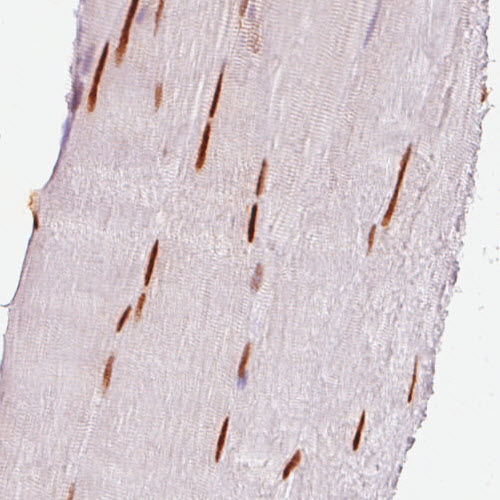

Immunohistochemistry analysis in human skeletal muscle and liver tissues using AMAb90544 antibody. Corresponding SIX1 RNA-seq data are presented for the same tissues.